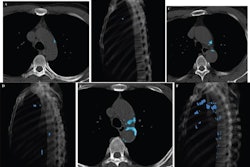

![]() |

| Noncontrast images of the thorax in a patient presenting with dyspnea demonstrate bilateral pleural effusions and four-vessel coronary calcification (i.e., the left main, left anterior descending, circumflex, and right coronary arteries). Images courtesy of Kim Williams, MD. |

Three experienced readers working independently reviewed all of the images for cardiovascular findings. According to the results, coronary calcium was present in 202 patients (59% of the group), but coronary artery calcium was recorded as being present in the final radiology report in just 44% of patients with calcium.

As for the most dangerous arterial segments in which to have stenoses, aka "the widowmakers," calcium was visible in the left main coronary artery in 139 patients but was reported in only 0.7% of the cases, Williams said. Calcium was visible on review of the left anterior descending artery images in 188 patients, but it was reported by name in only 1.6%.

Among patients with visible calcifications that were reported at review, only six of 612 calcified arteries were actually specified by name, including:

- 1 of 138 left main arteries with calcium

- 3 of 187 left anterior descending arteries with calcium

- 1 of 137 circumflex arteries with calcium

- 1 of 150 right coronary arteries with calcium